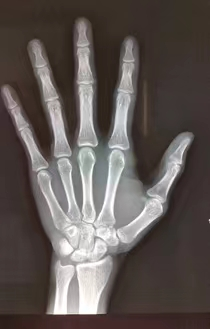

什么是骨龄片?拍摄骨龄片有什么作用?骨龄片是拍摄左手腕部的X光片。通过骨龄片,观察骨化中心出现的时间、数目、形态变化及其融合时间,判断骨骼实际发育程度,来评估生物学年龄——骨龄。

骨骺融合的骨龄图